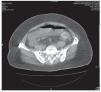

Ingresó al Instituto Nacional de Ciencias Médicas y Nutrición por dolor abdominal de características ya descritas. A la exploración física con dolor abdominal difuso a la palpación profunda y peristalsis disminuida. Los exámenes de laboratorio con 12,000/mm3, neutrófilos de 85%, pruebas de función hepática normales. Se le realizó una placa simple de abdomen con dilatación de asas de intestino delgado y aire en la vesícula biliar (Figura 1). Se le realizó una tomografía computada (TC), la cual mostró dilatación de asas de intestino delgado proximal, imagen hiperdensa intraluminal y zona de transición a este nivel (Figura 2). Se realizó laparotomía exploradora en la cual se evidenció un lito gigante de aproximadamente 6 cm de diámetro en el yeyuno proximal, se le realizó enterotomía con extracción del lito y cierre primario en dos capas (Figura 3).

Figura 2.Tomografía computada que muestra dilatación de asas de intestino delgado proximal, imagen hiperdensa intraluminal y zona de transición a este nivel